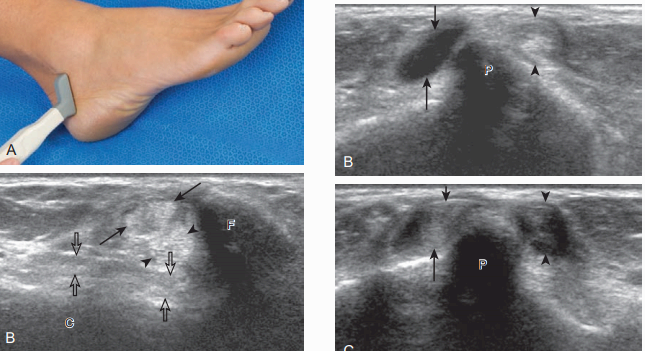

검사할 구조물은 종아리근힘줄과 가쪽인대이다. 검사는 먼저 가로면에서 가쪽복사보다 위-뒤쪽에서 시작한다. 이곳에서 짧은 종아리근의 힘살과 힘줄을 확인할 수 있다. 바로 옆에는 긴 종아리근힘줄이 있는데, 이 위치에서 긴 종아리근의 힘살은 보이지 않는다. 탐촉자를 위에서 아래로 이동하면, 짧은 종아리근 힘살이 점차 작아져서, 종아리뼈 끝에서는 두 개의 힘줄(짧은 종아리 및 긴 종아리힘줄)만 보인다. 만약 짧은 종아리근 힘살이 종아리뼈 끝보다 아래에서 보이면 이는 정상 변이로서 낮게 위치한 짧은 종아리근힘살(low lying muscle belly of the peroneus brevis)이라고 부르며 힘줄 째짐과 연관이 있기도 하다. 짧은 종아리힘줄은 종아리뼈의 뒤에 바로 붙어 있고 긴 종아리근힘줄은 짧은 종아리근보다 좀 더 뒤쪽에 있다. 얇고 높은 에코의 종아리근지지띠(peroneal retinaculum)가 힘줄을 덮고 있으며, 종아리뼈의 뒤-가쪽에 붙는다. 탐촉자를 종아리뼈의 끝 부분에서 발꿈치뼈 뒤로 비스듬히 놓으면, 발꿈치종아리인대(calcaneofibular ligament)가 종아리힘줄보다 깊은 곳에서 보인다.

종아리힘줄의 짧은 축 영상은 힘줄의 세로 째짐(longitudinal split tear)을 찾는데 적합하기 때문에 매우 중요하다. 종아리근힘줄이 종아리뼈에 대하여 가쪽 또는 앞쪽으로 탈구되는 것을 검사할 때 동적검사가 매우 유용하다. 탐촉자를 종아리뼈 뒤에 가로면으로 놓고, 환자의 발목을 뒷굽힘 또는 바깥돌림하면 힘줄 탈구를 유발할 수 있다. 이런 동적검사를 하는 도중에는 탐촉자를 너무 강하게 누르지 말아야 한다. 강하게 누르면 종아리근힘줄의 움직임을 방해할 수 있기 때문이다. 만약 종아리근지지띠가 정상이면 종아리근은 종아리뼈보다 항상 뒤쪽에 있어야 한다.